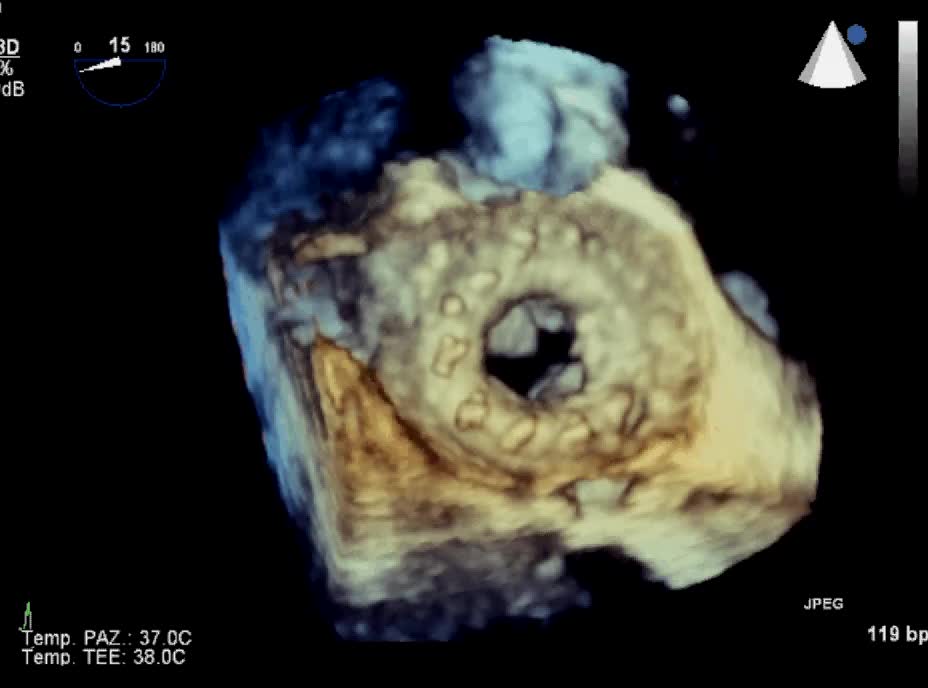

Protesi biologica mitralica Carpentier 25Autore: Daniela Torta

Categoria: Videoalbum

Parole chiave: biologica diagnosi ecotee3d protesi -